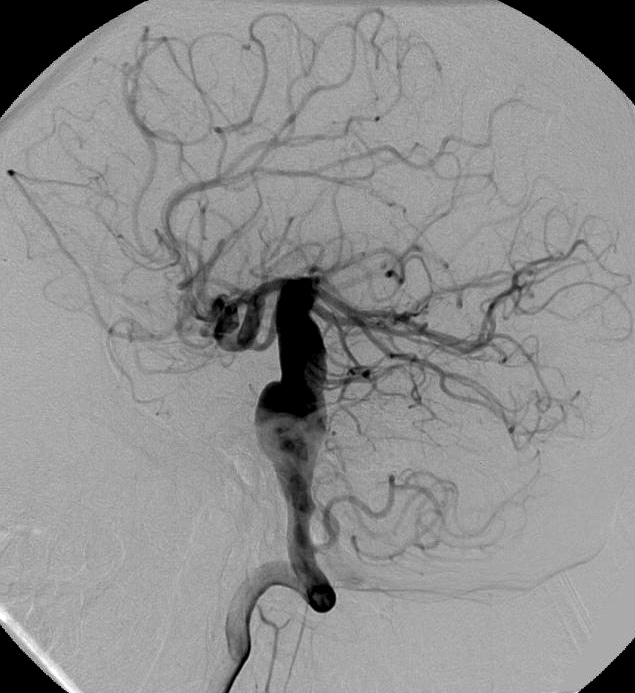

Снимки и иллюстрации микроаневризм сосудов головного мозга